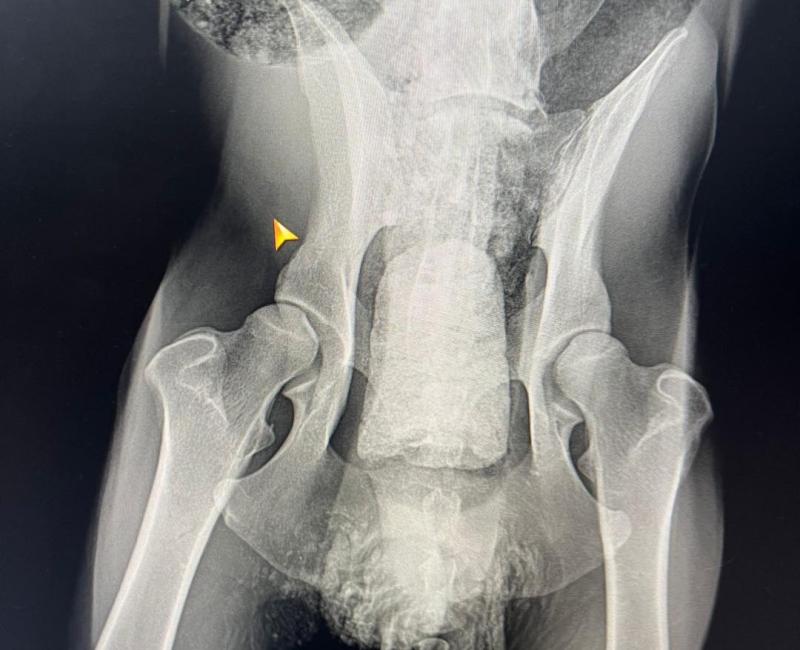

Ella, poyada por algunas compañeras gestoras de colonias, lo llevaron al vete de urgencias. Le hicieron análisis y radiografías. También tuvieron que sedarlo para extraer un tapón que tenía de huesos, pelos y mil cosas más que obstruía la salida anal…

23 Mayo de 2023: El día que la policía le retiró a Terry a su dueño. Aquí podéis ver lo delgado que está y la inflamación de la barriga, y por supuesto, la lucha que tiene por mantenerse en pie...